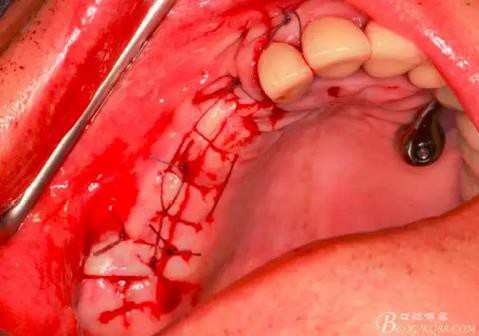

習慣性的在竇膜下貼服一張膜保護。

生物膜平整地貼附在竇膜上。

同種異體骨松質(zhì)骨與Bio-oss骨粉混合。

用骨粉充填器植入骨粉。

14,15牙位植入兩顆植體,6,7牙位骨高度嚴重不足,且骨密度低,無法給植體提供良好的初期穩(wěn)定性,需二期植入。13牙位骨寬度不足,沒有植骨、植植體,修復時用后面4顆連冠加一顆3的游離臂是沒有問題的。當然這里我們不去討論這個方法的合理性,我們今天的話題是改良式外提升技術的應用。